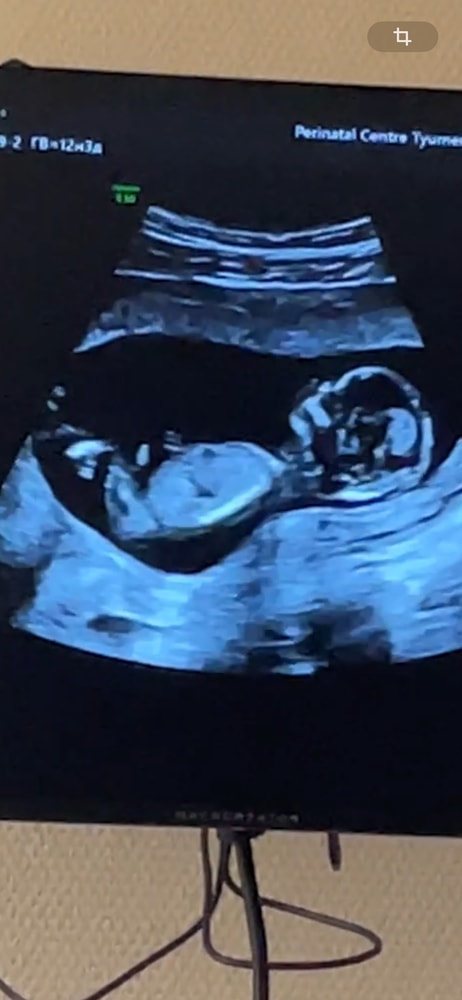

Барышня 90%

Наверное девочка

Но я встречала тут пост,девочка такой же ракурс малыша и половой бугорок выкладывала,а на 2 скрининге оказался мальчик.🤷♀️

Maryli , Да-да, все в один голос в комментариях писали про девочку и я была прям уверенна в этом. Вот потом мы удивились)))